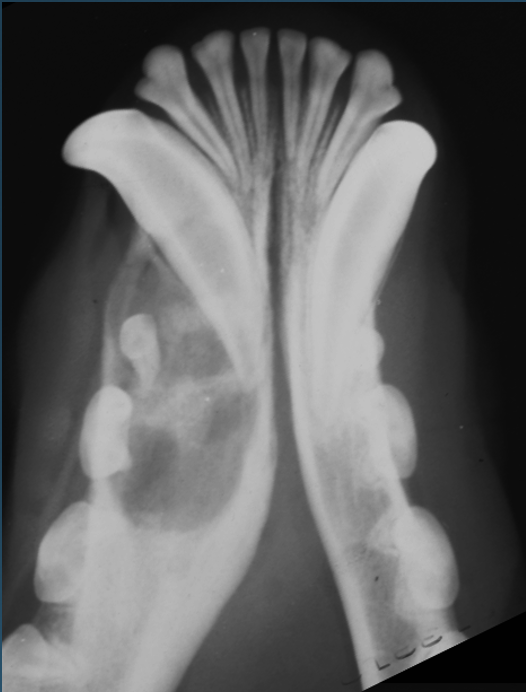

What is shown in these images?

nasal neoplasia: -soft tissue mass causing facial deformity -marked maxillary osteolysis -complete loss of turbinates; left more than right